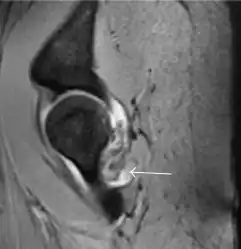

Most of the angles and measurements described in the plain radiograph section can be accurately reproduced on MRI. In addition, the superiority of MRI resolution with intra-articular contrast allows detection of labral and chondral abnormalities that may influence the choice of medical, percutaneous, or surgical management (Figure 9).[1]

Figure 9:

Sagittal T1 weighted image showing anterosuperior labral tear.[1]

Sagittal T1 weighted image showing chondral lesion.[1]

Sagittal CT-arthrography showing posteroinferior chondral injury.[1]

Coronal CT-arthrography (d) showing ligamentum teres tear.[1]